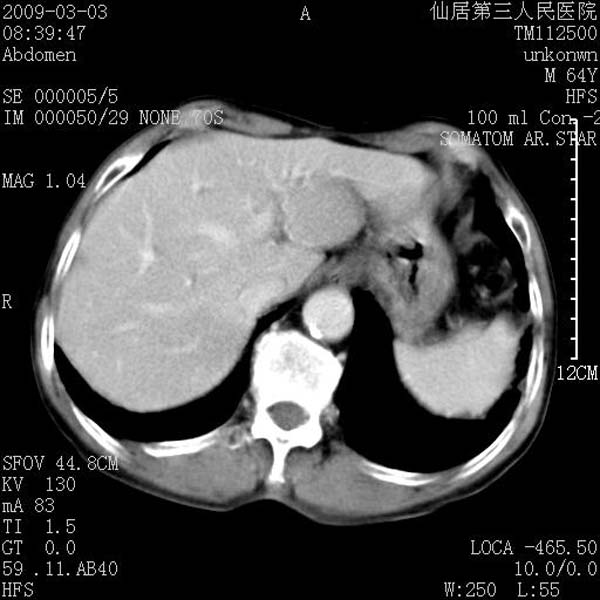

标题: CT18469:男性,64y,体检B超示肝脏低回声肿块,有胃溃疡手术 [打印本页]

标题: CT18469:男性,64y,体检B超示肝脏低回声肿块,有胃溃疡手术

患者,男性,64y,体检b超示肝脏低回声肿块,有胃溃疡手术史。

从平扫及增强的特点来看,支持肝脏腺瘤并出血。

支持肝脏腺瘤并出血。期待结果。

考虑肝静脉韧带裂区良性占位性病变(囊肿?)。

考虑肝囊肿并出血可能性大.

支持肝脏腺瘤并出血。期待结果

考虑高密度囊肿可能性大